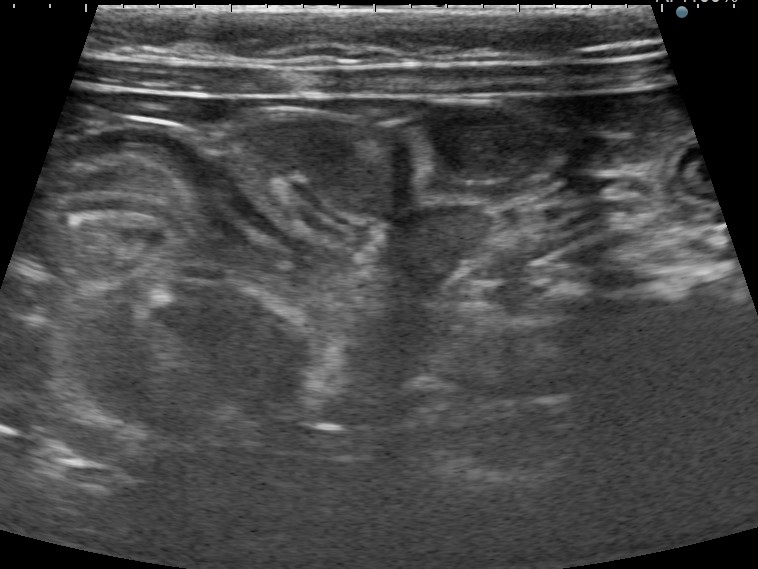

レントゲン検査およびエコー検査にて胃腸内にひも状異物が観察され、特徴的な腸管の蛇行(アコーディオン陰影)を認めました。

腸管のアコーディオン陰影像